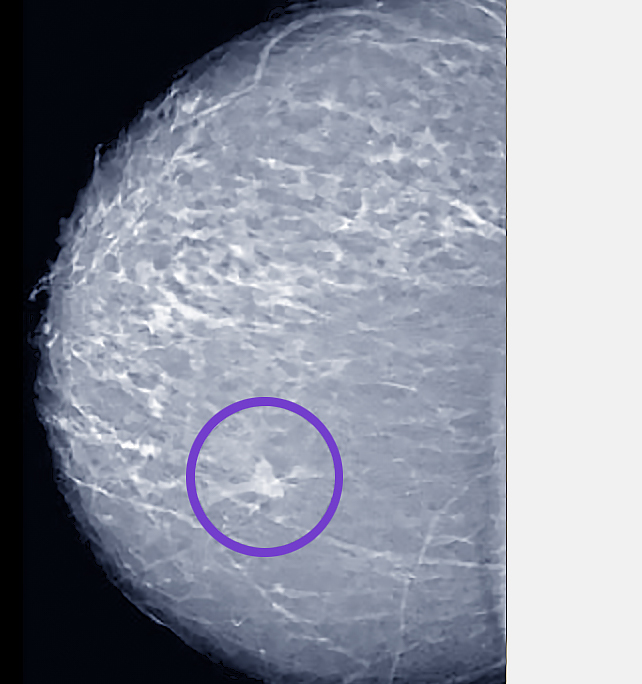

What are suspicious findings in a mammogram?

Suspicious findings on a mammogram require further evaluation to rule out breast cancer. These findings include:

Suspicious Indicators:

- Masses or lumps with irregular shapes or margins, which may suggest cancer.

- Microcalcifications, or tiny calcium deposits, clustered in a specific area, indicating potential malignancy.

- Asymmetry where one breast shows areas that differ significantly from the other.

- Architectural distortion, where the normal structure of breast tissue appears altered.

If any of these signs are present, your radiologist will likely recommend additional imaging, such as an ultrasound or MRI, and possibly a biopsy to determine the nature of the findings.

It’s important to remember that not all suspicious results indicate cancer, but they do warrant further investigation to ensure your breast health. Early detection through careful screening increases the chances of successful treatment, so follow up promptly if you receive such a report.